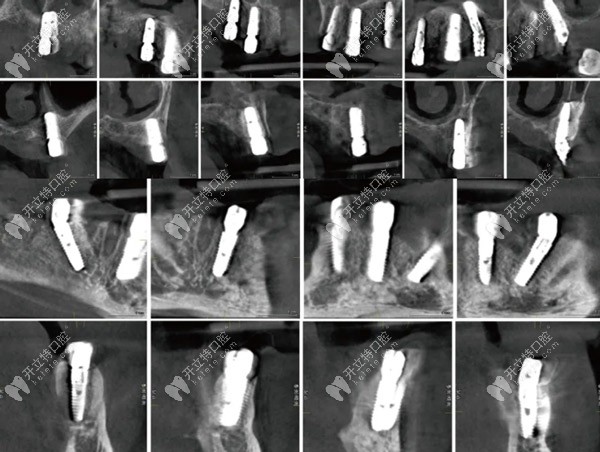

手術(shù)導(dǎo)板口內(nèi)試戴后,必蘭局麻后上頜導(dǎo)板固定,16,13,11,21,24,26位點(diǎn)先鋒鉆備洞,骨修整后分別植入0sstem Ts植體4.5-10mm(2顆)、4.0-11.5mm(3顆)、4.5-13mm各一枚。,充分利用牙槽嵴頂、鼻底及上頜竇底的皮質(zhì)骨達(dá)到良好的初期穩(wěn)定性。

術(shù)后即刻CBCT種植體冠狀、矢狀面影像

術(shù)后即刻CBCT種植體冠狀、矢狀面影像▲

下頜導(dǎo)板固定后先鋒鉆備洞,骨修整于35,32,42,45位點(diǎn)植入Osstem Ts植體4.5-13mm(2顆)、4.0-11.5mm(2顆)所有的植體初期穩(wěn)定性均達(dá)到35Ncm以上。安裝復(fù)合基臺(tái)(30Ncm)及保護(hù)帽縫合。

拍攝CBCT檢查各植體三維位置后,取下復(fù)合基臺(tái)保護(hù)帽,安裝開口印模帽并以GC技工樹脂做剛性連接,取硅膠印模。